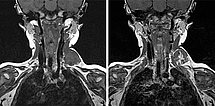

In coronal MRI (left image: T2-weighted, right image: non-enhanced T1-weighted), the venous malformation (VM) is very well delineated. It is strongly hyperintense in the T2 image, whereas it is isointense to the musculature in the non-enhanced T1 image. The signal intensity is typical of the character of a slow-flow lesion.

In coronal MRI (left: T2-weighted, right: T1-weighted non-enhanced) slightly more dorsally, a larger thrombus within the venous malformation is very well delineated. In the T2 image, this is hypointense compared to the severely hyperintense venous malformation. In the non-enhanced T1 image it is slightly more hyperintense than the surrounding hypointense venous malformation.